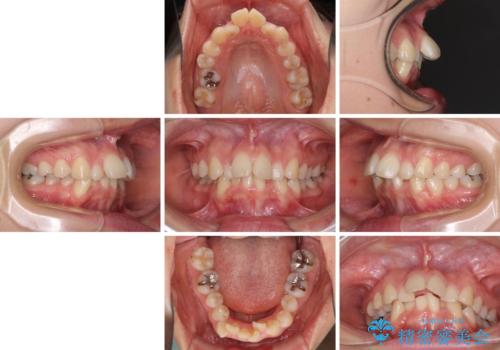

デコボコで飛び出した前歯 ワイヤー装置による抜歯矯正

- 上下前歯のデコボコと、飛び出した前歯を気にして来院された患者様です。

口元を積極的に引っ込めるために、上下左右の小臼歯計4本を抜歯することとしました。

咬み合わせが深く、咬合力強いため、補助装置を使用しながら積極的に口元を下げることとしました。

矯正治療前の咬み合わせで、前歯がすり減ってしまい、歯列が整ったときに先端がガタガタになってしまったため、矯正治療後に形態修正を行いました。